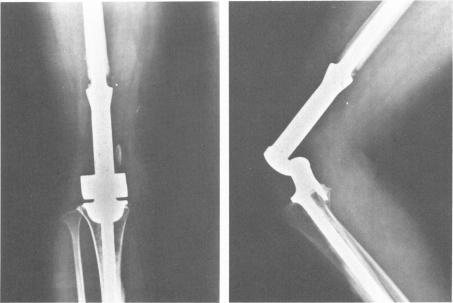

En block surgery for osteogenic sarcoma: analysis and review of ninety operative cases.

Bull N Y Acad Med. 1984 Sep;60(7):748-58.